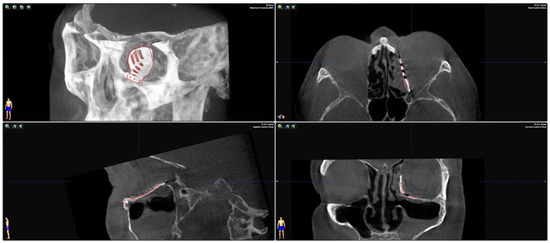

2. Methods and Results

2.2. Surgery